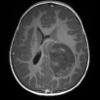

ETMR - Embryonal Tumor Multilayered Rosettes (9)